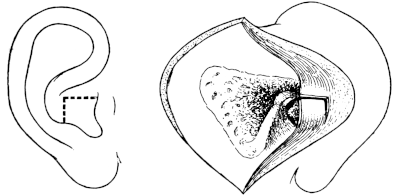

| 228. | Post-meatal Skin Flaps | 401 |

| 229. | Post-meatal Skin Flaps | 401 |

| 230. | Closure of Wound after ‘Radical’ Mastoid Operation | 401 |